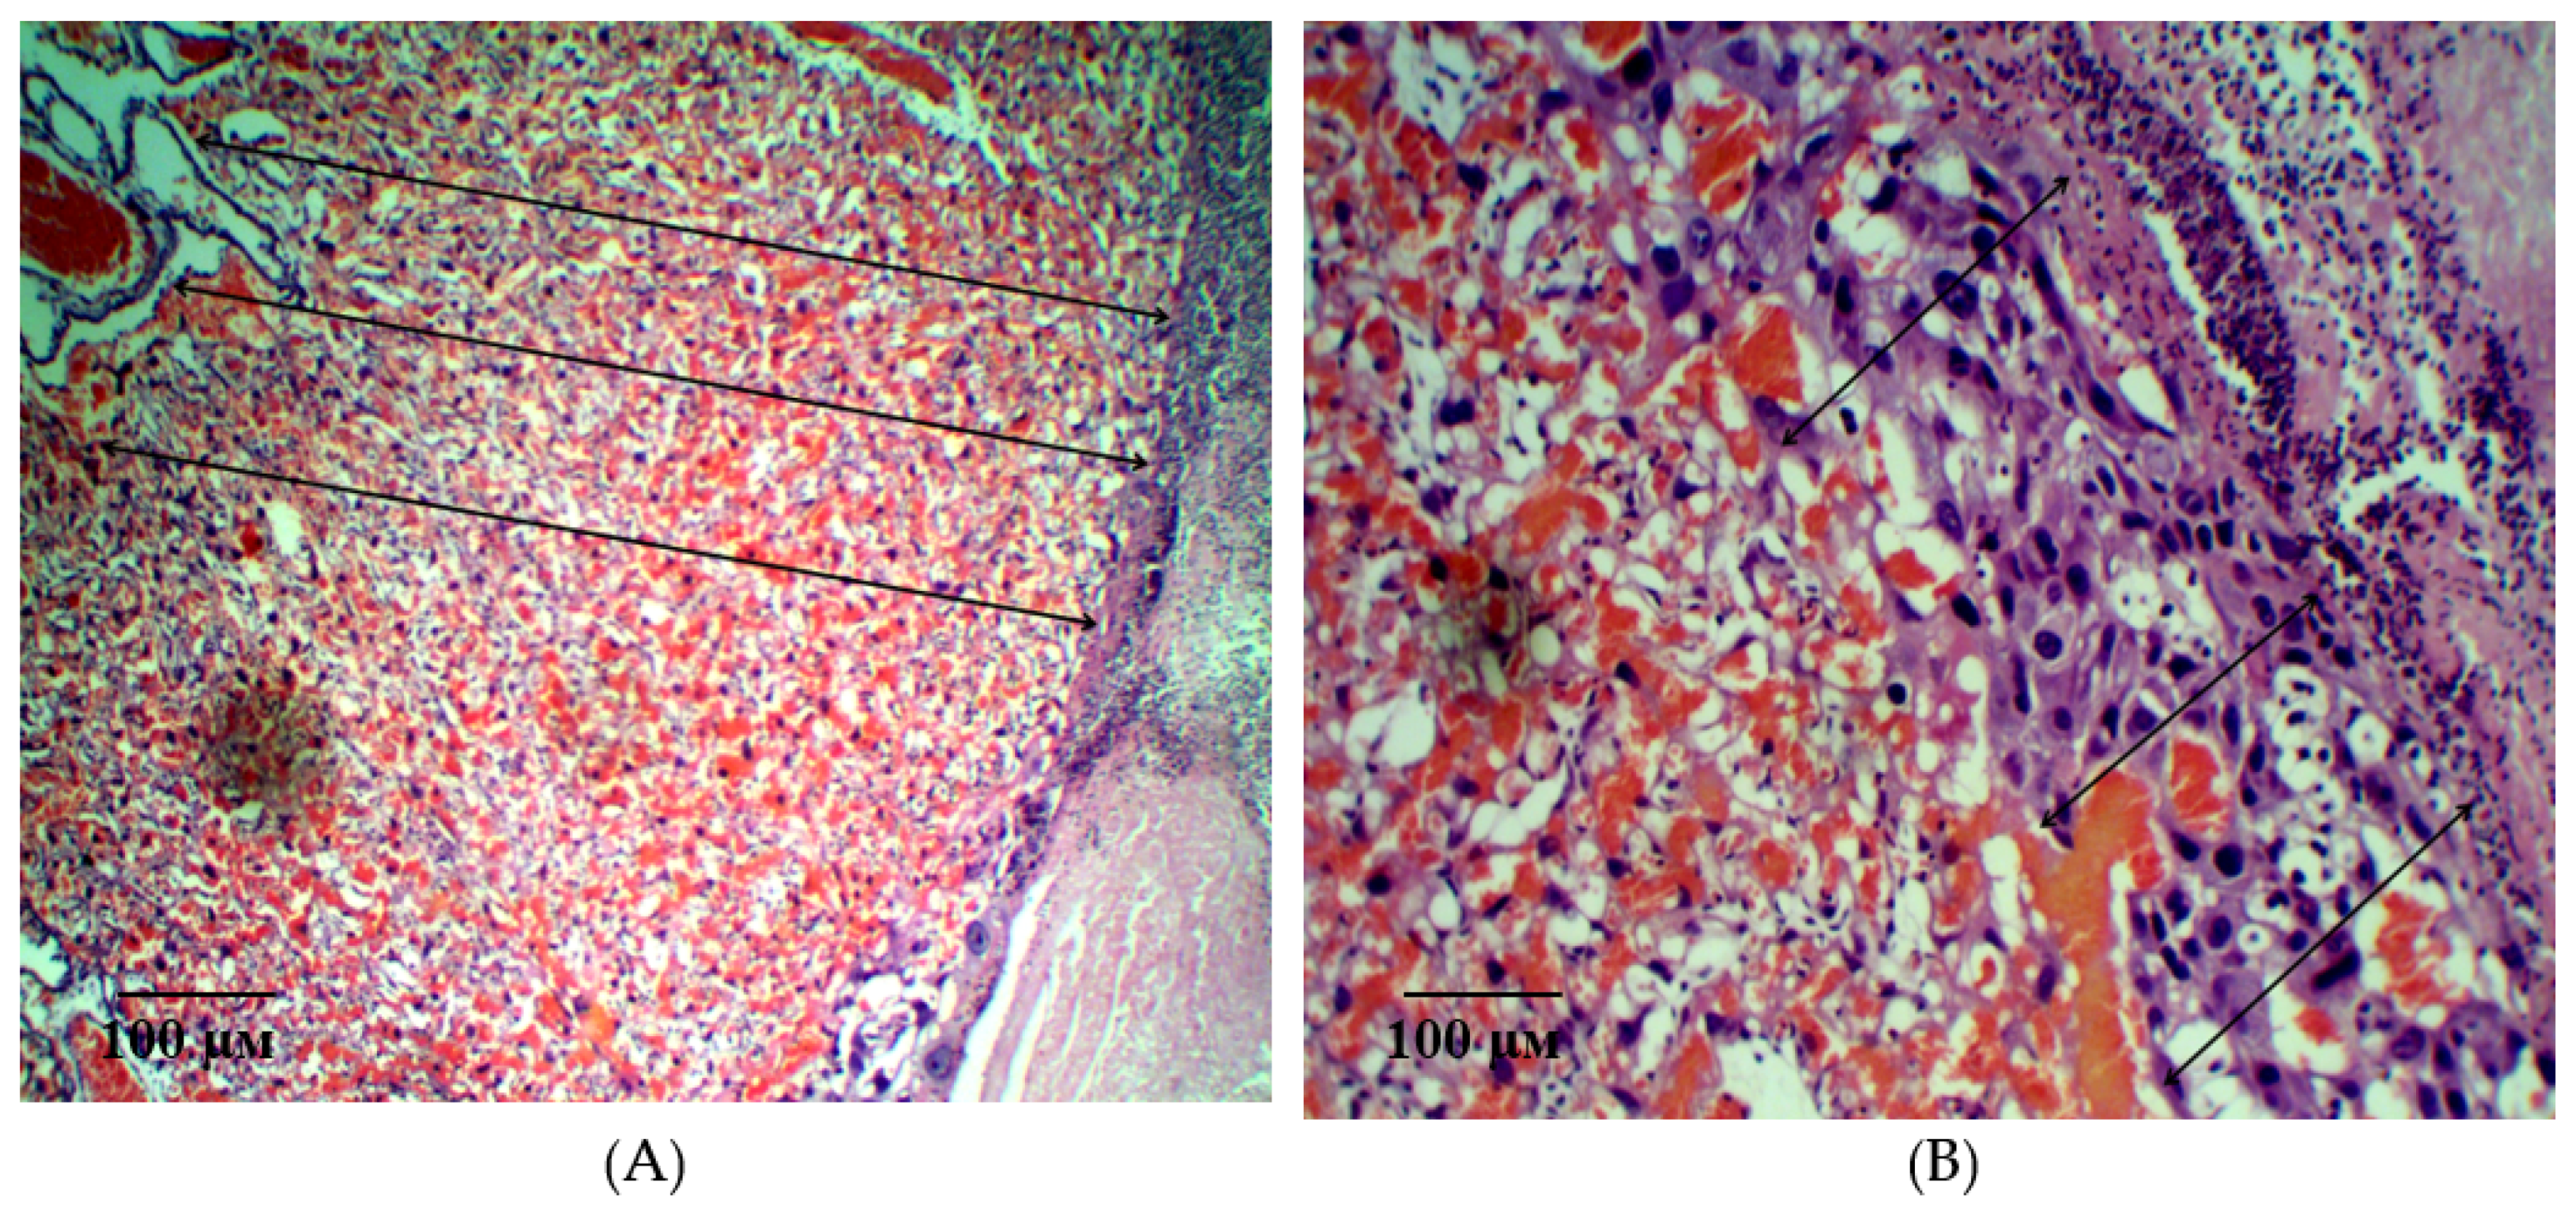

2.2. Results of Histological Examination

| Group | Decidual Cell Density, /0.008 mm2 | Cell Dencity in the Fetal Placenta, /0.008 mm2 | Villi Diameter, ×10−3μm |

|---|---|---|---|

| Int | 114.2 ± 2.03 y | 236.9 ± 2.75 y | 32.18 ± 0.39 y |

| L-NAME | 22.3 ± 0.28 * | 78.5 ± 2.51 * | 16.79 ± 0.24 * |

| Epo (50 IU/kg) | 74.3 ± 0.73 *,y | 137.0 ± 4.17 *,y | 22.33 ± 0.16 *,y |

| pHBSP (10 μg/kg) | 67.7 ± 0.59 *,y | 92.3 ± 1.24 *,y | 21.01 ± 0.16 *,y |

| pHBSP (250 μg/kg) | 80.2 ± 0.75 *,y | 160.0 ± 3.22 *,y | 30.91 ± 0.17 *,y |